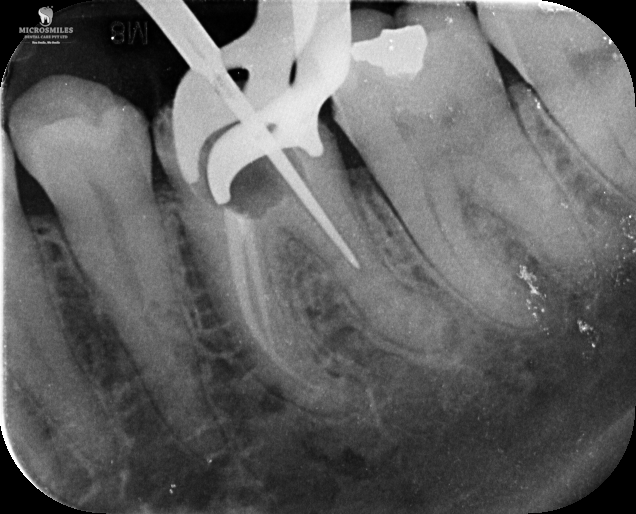

Our treatments are performed using advanced dental microscopes that magnify up to 25x- allowing us to identify previously hidden canals, fractures, or infected areas that standard tools may miss. This level of detail means faster, more accurate procedures and fewer surprises, giving your tooth the attention it truly deserves.

We streamline the retreatment process by using enhanced imaging, digital diagnostics, and precision tools-reducing unnecessary visits and helping you get back to normal faster.